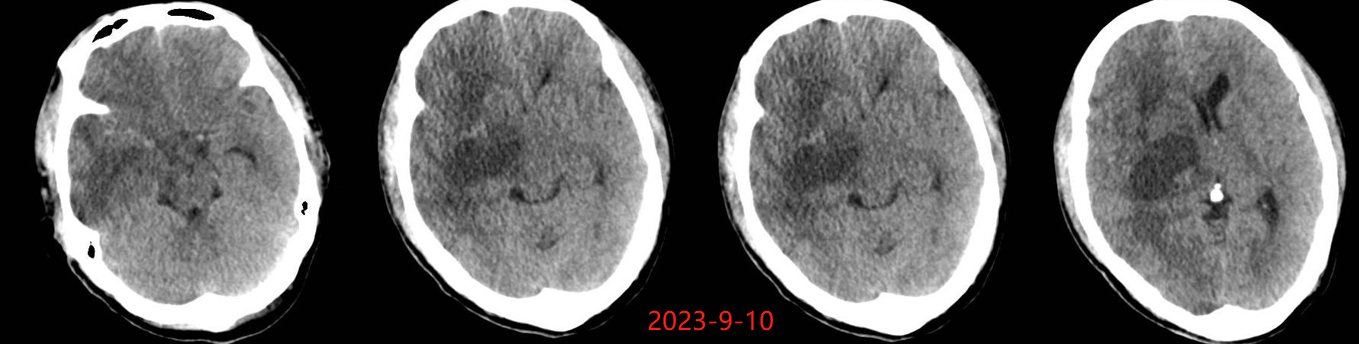

入院后于当地医院完善头颈部CTA检查未见明显血管发育异常,于2023-6-7行血肿钻孔引流术+脑室内颅内压监护探极置入术,引流一周后拔除引流管,期间未行尿激酶注射,患者反应情况逐渐好转,肌力未见明显改善。于出血后3周左右脑水肿基本消退后出院行康复治疗,治疗过程中患者肌力曾有所改善,左侧肢体肌力最好可达3级。术后3月左右患者一般状态逐渐变差,无发热,神志逐渐进展为昏睡状态,左侧肢体肌力1级,复查颅脑CT示水肿较前明显加重,颅脑MRI示右侧基底节区长T1长T2团块状病变,内有囊变,呈不均匀菜花样强化,考虑为高级别胶质瘤可能性大。遂行开颅病灶大部切除+去骨瓣减压术,术后病理提示高级别胶质瘤伴囊变,后续行同步放化疗STUPP方案,PTV:60Gy/30F/6周,替莫唑胺350mg化疗。患者右侧基底节区病灶相对稳定,2024-9-3复查颅脑MRI可见脑室内新发病灶。患者目前KPS 60分,神志清醒,精神差,反应迟钝,语言对答部分切题,右侧肢体自主活动,左侧肢体肌力2级。

胶质瘤出血灶周围水肿一般较广泛,同血肿期龄存在明显不符的征象,出血后早期即有明显水肿,此时并非血肿引起,而是肿瘤机械压迫、脑皮质受损,肿瘤细胞的分泌作用及细胞毒性等多因素共同作用所致,且水肿持续时间长。 高血压性脑出血的水肿一般在出血后 3 h 出现,48 h 达高峰,4 d 后开始逐渐消退,2-3 周后基本消失。该患者脑水肿出现的时间相对较早、重,且持续时间长,有别于一般的高血压脑出血。若该患者若第一次出血行钻孔引流时,术中能留取标本查到肿瘤脱落细胞,则会使该患者的诊断提前;当然对于该患者也不能完全排除单纯脑出血后,周围脑组织水肿缺氧等微环境的改变诱发胶质瘤的发生。总之,对于既往无脑出血高危因素且脑血管检查未见明显异常的脑出血患者,若脑水肿出现早且持续时间长,应警惕肿瘤卒中可能。